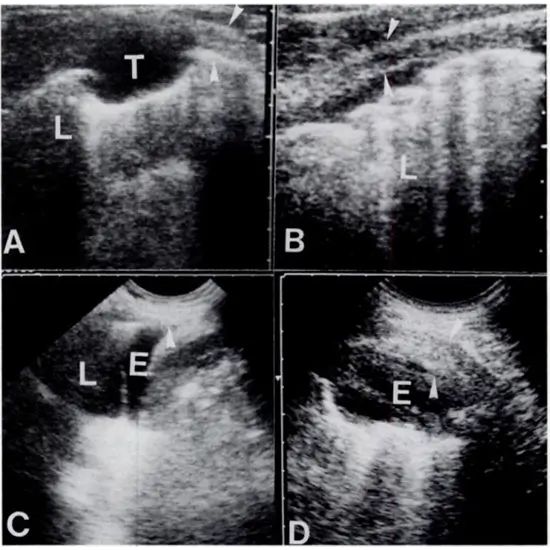

The characteristic appearance of pleural effusion on the ultrasound appears as complex non-septated black/anechoic and white lesions, complex black and white septated septae, or homogeneously white/echogenic lesions.